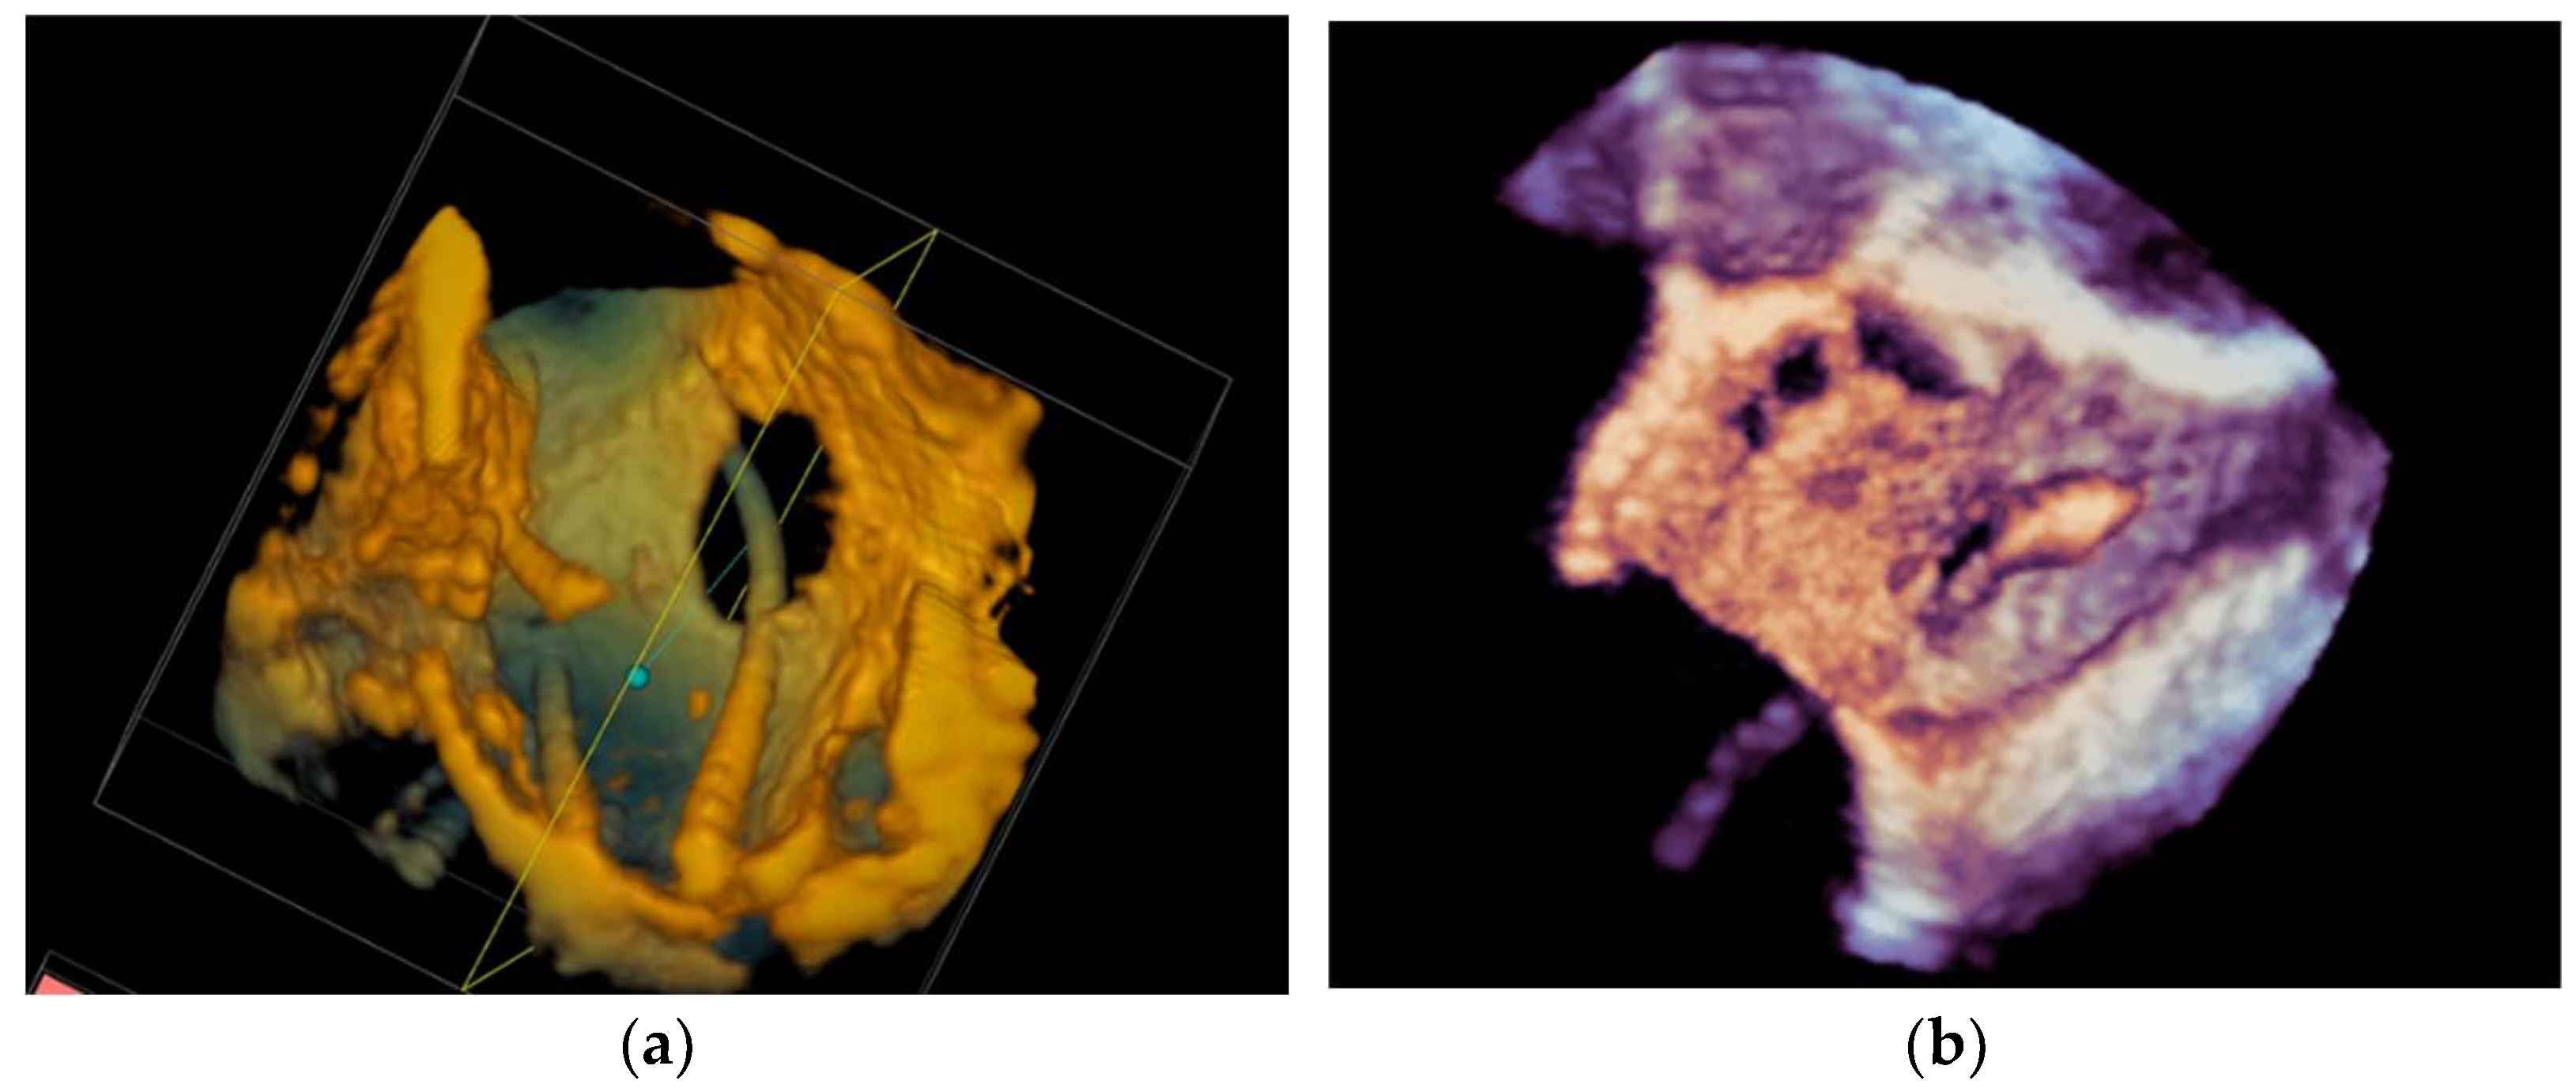

4.2.5. Paravalvular Leak Closure

4.2.6. Transcatheter Aortic Valve Replacement